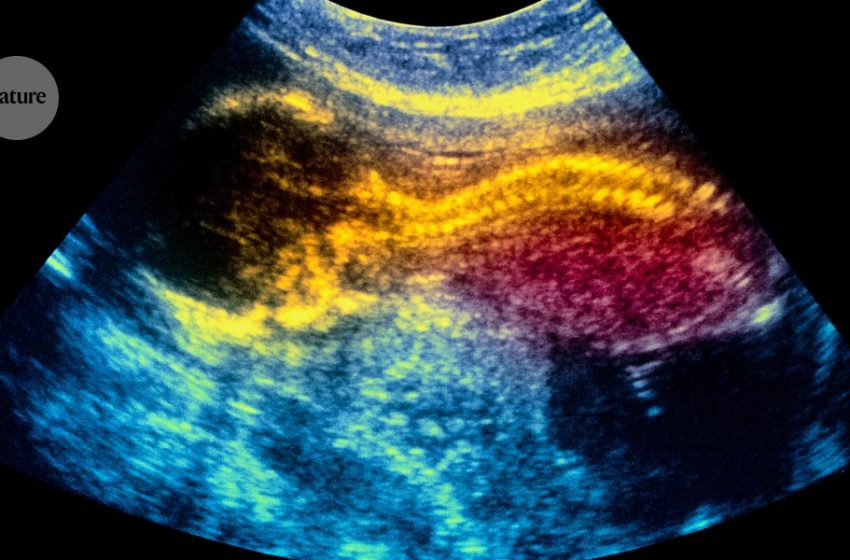

An in utero treatment using placenta-derived stem cells could treat infants with a neural-tube condition called spina bifida. Credit: Simon Fraser/Science Photo Library